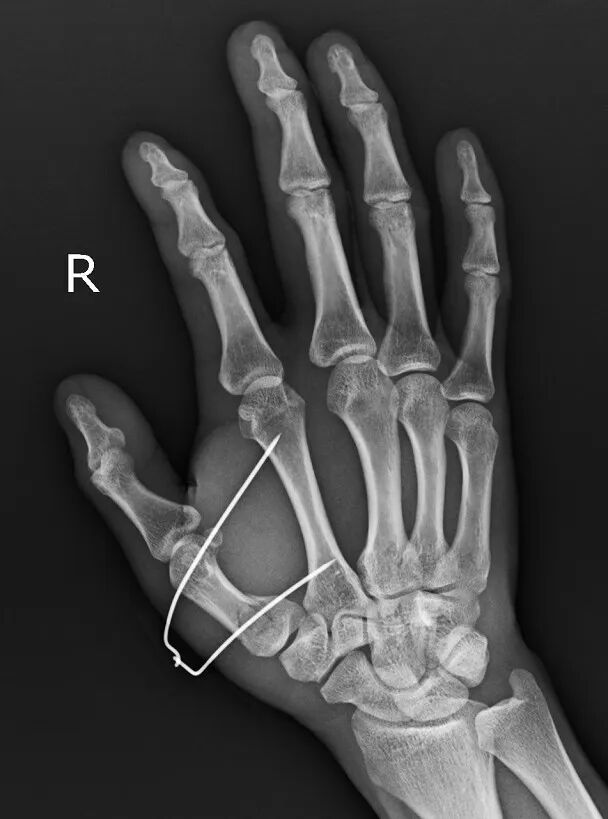

患者是52歲男性,因摔倒導致右手第一掌骨基底部骨折

手術前右手正斜位片

手術后次日復查左手正斜位片